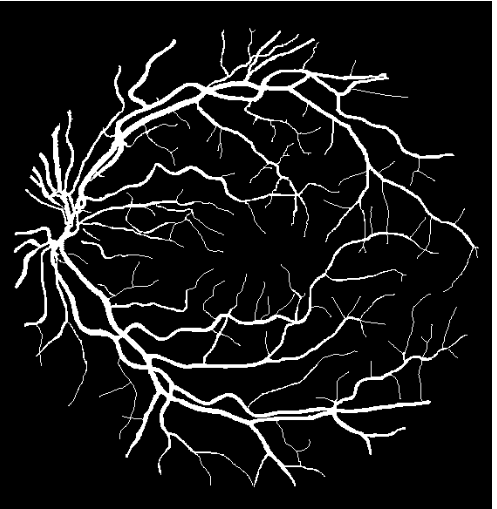

The CNN was trained and tested against the Digital Retinal Images for Vessel Extraction (DRIVE) database111http://www.isi.uu.nl/Research/Databases/DRIVE/, a standardized set of fundus images used to gauge the effectiveness of classification algorithms [24]. The images are 8 bits per RGBA channel with a 565584 pixel resolution. The data set comprises of 20 training images with manually delineated label masks and 20 test images with two sets of manually delineated label masks by the first and second human observers, as shown in Fig. 1. The images were collected for a diabetic retinopathy screening program in the Netherlands using a Canon CR5 non-mydriatic 3CCD camera with a 45° field of view [24].

The output of PixelBNN is a binary label mask, predicting vessel and non-vessel pixels thereby segmenting the original image. Each dataset contains a two experts’ manual delineations; the first was used as the ground truth for training the model and the second was used for evaluating the network’s performance against a secondary human observer. Independently, each dataset was used to train a separate model from scratch resulting in three sets of model parameters.